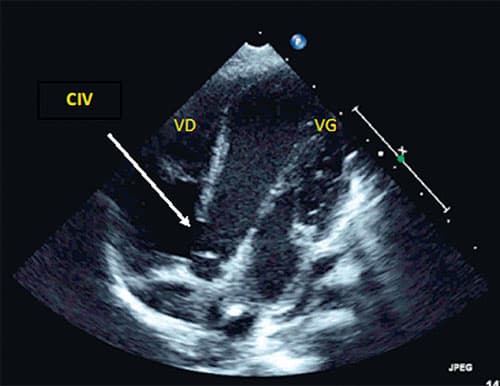

Fig. 11.5 ![]() Large communication interventriculaire (CIV) : échocardiographie transthoracique, incidence apicale des 4 cavités.

Large communication interventriculaire (CIV) : échocardiographie transthoracique, incidence apicale des 4 cavités.

CIV haute, du septum membraneux, de 10,5 mm de diamètre. VD : ventricule droit ; VG : ventricule gauche.